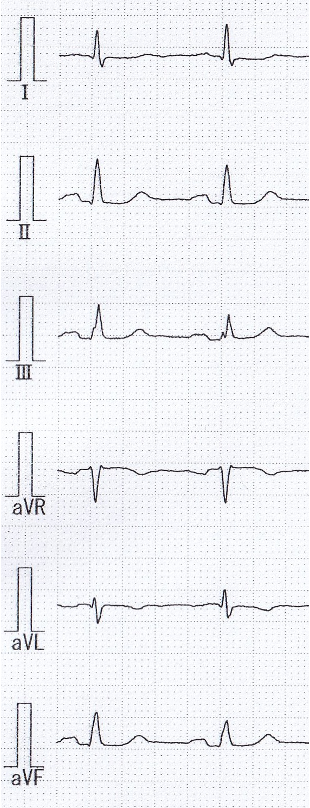

ECG: sinus,ST depression in I,aVL,V5,V6 leads.UCG:LVEF 60%,wallmotion anteroseptal mid~apex hypokinesis, inferior severe hypokinesis. No ventricular wall thinning. No significant valvular disease observed.Blood examination:HbA1c 9.1%,LDL-chol 101 mg/dL,Cre 1.23 mg/dL,eGFR 47.8,Hb 15.8 g/dL,CPK 51 IU/L,BNP 109.1 pg/mL.Exercise electrocardiography: ST depression in Ⅱ,Ⅲ,aVF leads.